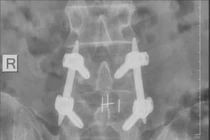

Phương pháp bắt vít qua da điều trị thoát vị đĩa đệm cột sống ít xâm lấn này giúp bệnh nhân giảm đau, vận động sớm và phục hồi nhanh hạn chế các biến chứng.

Vừa qua, khoa Ngoại Thần Kinh Bệnh viện Đa khoa Xuyên Á Vĩnh Long đã phẫu thuật thành công điều trị thoát vị đĩa đệm bằng phương pháp bắt vít qua da cho bệnh nhân T.T.K.L., (61 tuổi, ngụ tại Vĩnh Long). Đây là phương pháp điều trị tiên tiến, ít xâm lấn giúp người bệnh nhanh chóng hồi phục.

Bệnh nhân L. đau cột sống thắt lưng đã nhiều năm, điều trị và uống thuốc nhiều nơi mà không giảm. Gần đây lưng cô bắt đầu đau nhiều hơn trước, cơn đau lan xuống mông và hai chân, làm hạn chế vận động và gây ảnh hưởng đến đời sống và sinh hoạt hằng ngày của bệnh nhân.